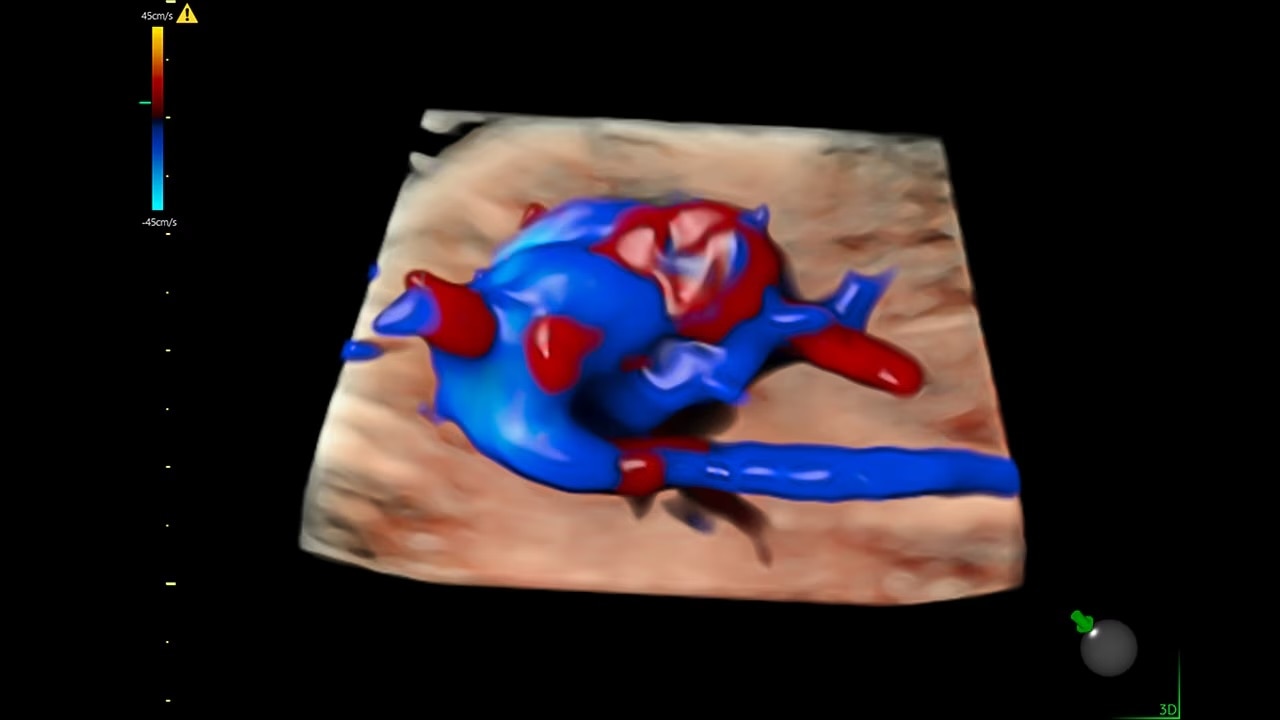

Next level color Doppler that delivers exceptional sensitivity for easy, fast visualization of blood flow, displaying a 3D like appearance as seen in this 27-week fetal heart.